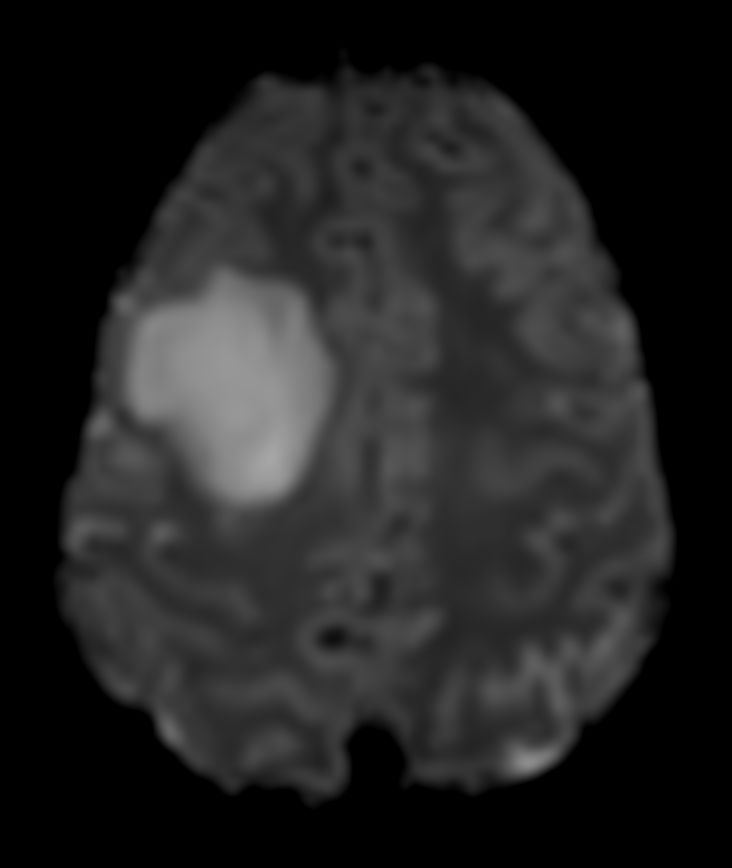

Diffusion (b1000)

-